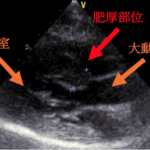

• #2 閉塞性肥大型心筋症ステージB1

循環器科

#2 閉塞性肥大型心筋症ステージB1【循環器科】

<症例情報>雑種猫 2歳7か月齢 去勢済みの男の子 心雑音を認める 主訴:心雑音の精査のた…